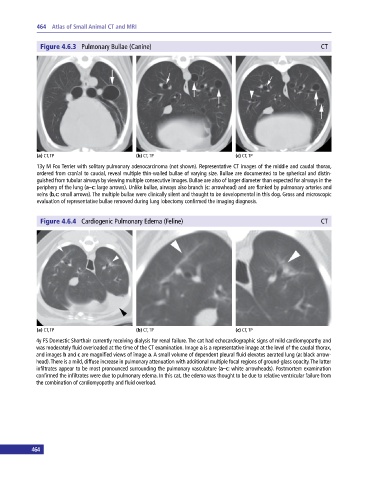

Figure 4.6.3 Pulmonary Bullae (Canine) CT

(a) CT, TP (b) CT, TP (c) CT, TP

13y M Fox Terrier with solitary pulmonary adenocarcinoma (not shown). Representative CT images of the middle and caudal thorax,

ordered from cranial to caudal, reveal multiple thin‐walled bullae of varying size. Bullae are documented to be spherical and distin-

guished from tubular airways by viewing multiple consecutive images. Bullae are also of larger diameter than expected for airways in the

periphery of the lung (a–c: large arrows). Unlike bullae, airways also branch (c: arrowhead) and are flanked by pulmonary arteries and

veins (b,c: small arrows). The multiple bullae were clinically silent and thought to be developmental in this dog. Gross and microscopic

evaluation of representative bullae removed during lung lobectomy confirmed the imaging diagnosis.

Figure 4.6.4 Cardiogenic Pulmonary Edema (Feline) CT

4y FS Domestic Shorthair currently receiving dialysis for renal failure. The cat had echocardiographic signs of mild cardiomyopathy and

was moderately fluid overloaded at the time of the CT examination. Image a is a representative image at the level of the caudal thorax,

and images b and c are magnified views of image a. A small volume of dependent pleural fluid elevates aerated lung (a: black arrow-

head). There is a mild, diffuse increase in pulmonary attenuation with additional multiple focal regions of ground‐glass opacity. The latter

infiltrates appear to be most pronounced surrounding the pulmonary vasculature (a–c: white arrowheads). Postmortem examination

confirmed the infiltrates were due to pulmonary edema. In this cat, the edema was thought to be due to relative ventricular failure from

the combination of cardiomyopathy and fluid overload.